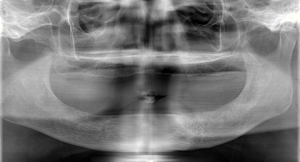

歯がある人

精密義歯装着5年後

顎の骨の高さが維持されています。